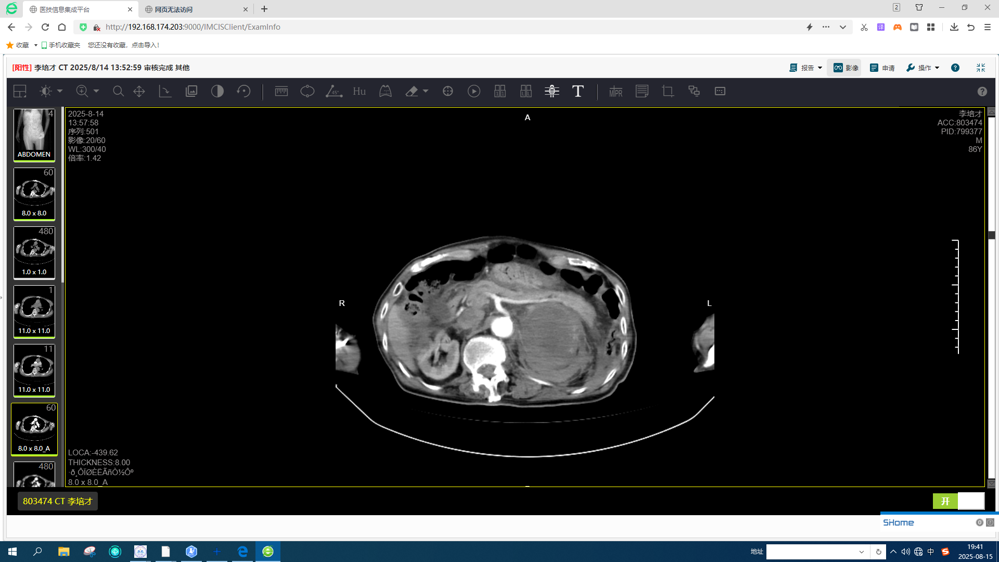

86岁的李伯因“腹痛2天”入院,入院后查血常规提示重度贫血(血红蛋白:58g/L),进一步完善CT增强扫描显示:左侧肾上腺肿瘤破裂出血,病情危急!经与患者和家属沟通,同意尽快做微创介入手术。

CT增强显示左侧肾上腺肿瘤破裂出血